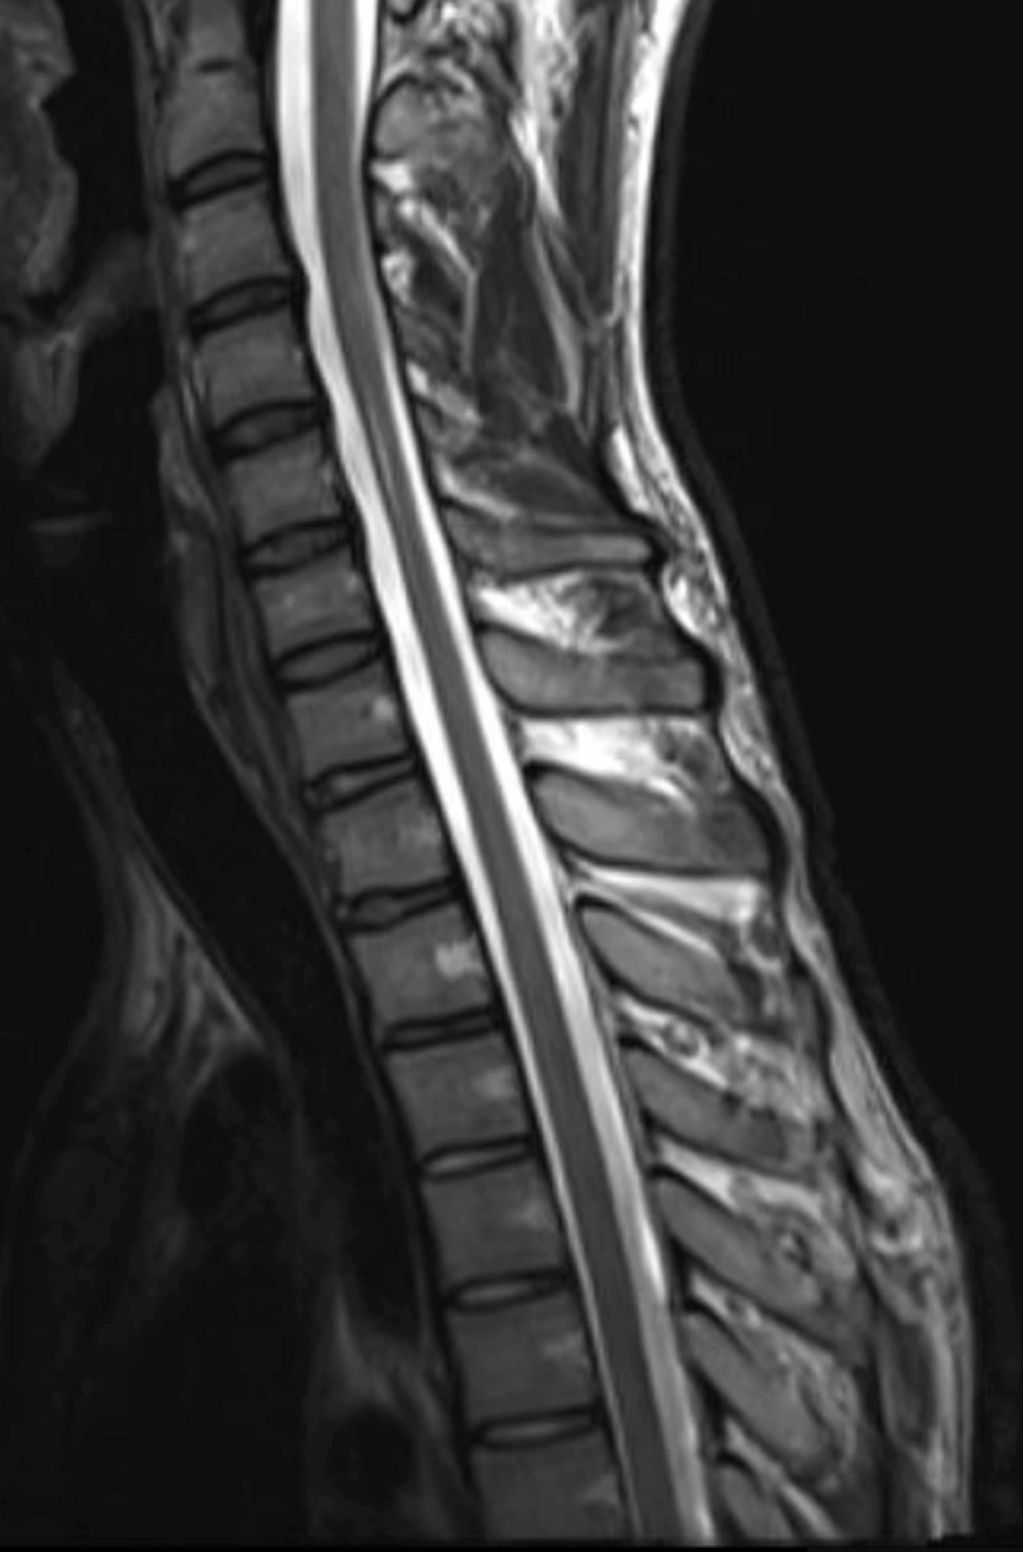

Neutral position: Sagittal T2 MRI of cervical spine showing normal canal dimensions

Flexion MRI: Sagittal T2 weighted image of cervical spine showing posterior dural laxity/increase in laminodural space with flattening of the cord